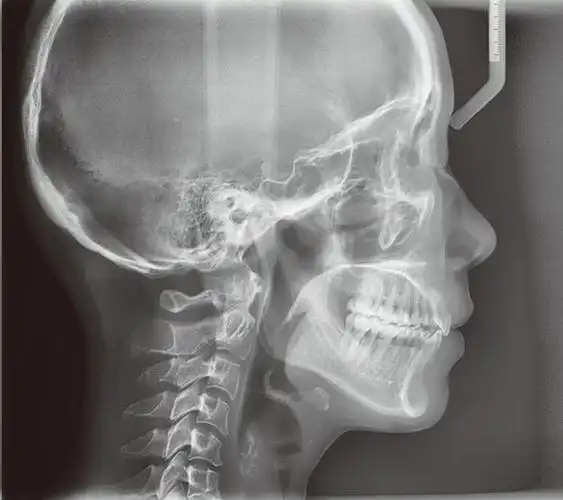

图22治疗后头颅侧位片,显示覆19覆盖正常,牙轴位置正常图23治疗后头